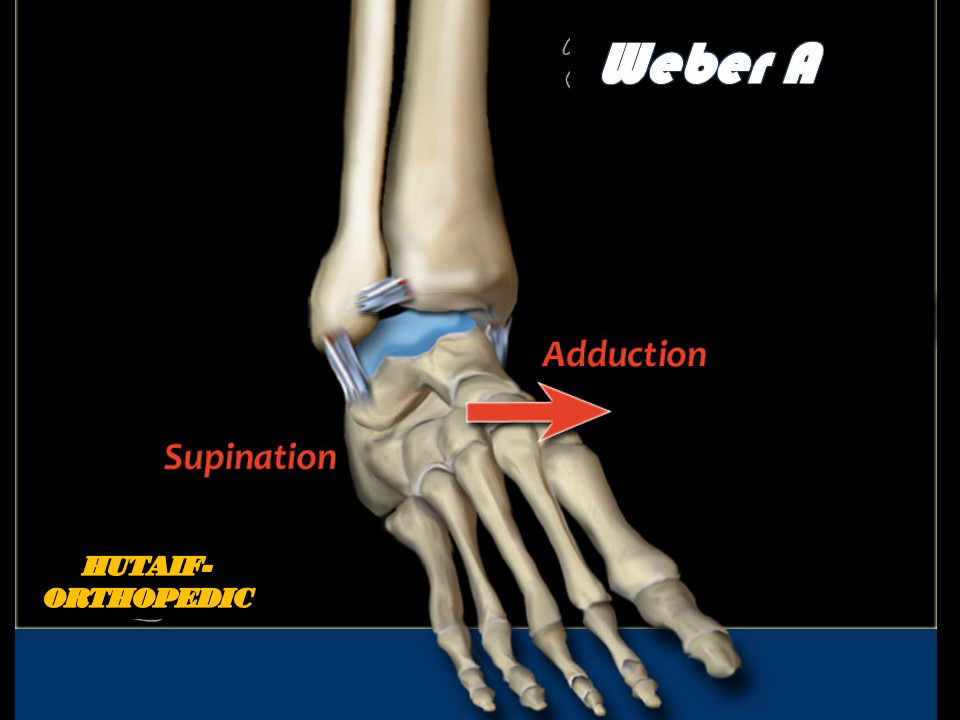

Explore Weber A ankle fractures: extra-articular fibula fractures below the syndesmosis. Understand their sta…

Explore the Danis-Weber classification for ankle fractures, its historical context, and critical surgical ana…